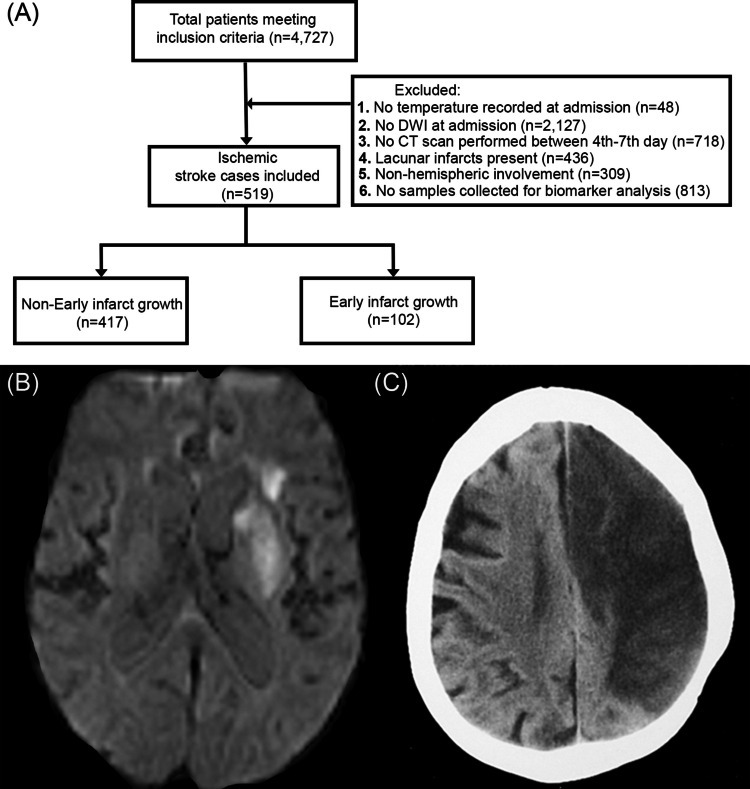

缺血性卒中(IS)后24小时内的热疗与不良预后相关。我们试图确定血脑屏障(BBB)通透性是否有助于热疗和早期梗死生长(EIG)之间的关系。对前瞻性脑卒中生物库进行回顾性分析。EIG定义为入院时弥散加权成像确定的初始体积(mL)与第4 -7天对照CT图像确定的体积(mL)之间的百分比差。热休克定义为24小时内腋窝温度≥37.5℃。采用ELISA法测定可溶性肿瘤坏死因子样细胞凋亡弱诱导剂(sTWEAK)血清水平。519例患者(45.6%为女性)中有102例(19.7%)出现EIG。腋窝体温与EIG呈线性相关(Pearson’s r = 0.46;P < 0.001)。sTWEAK血清水平的c统计量为0.74 (95% CI: 0.69-0.79),预测EIG的最佳临界值为bb0 3000pg /mL。此外,微量白蛋白尿水平与sTWEAK水平密切相关(Pearson’s r = 0.75;P < 0.001)。在多变量分析中,观察到EIG与高热的独立关联(调整OR为24.21;95% CI: 12.03-39.12), sTWEAK水平bb0 3000pg /mL(调整OR为16.43;95% CI: 3.71-72.70),白质变病(调整OR 10.42;95% CI: 2.68-39.08)和微量白蛋白尿(调整OR 1.02;95% ci: 1.00-1.12)。在我们的队列中,热疗与IS后的EIG独立相关。微量白蛋白尿、白质变和sTWEAK也与EIG相关,这表明EIG与血脑屏障通透性增加有关。

Hyperthermia within the first 24 h following ischemic stroke (IS) has been associated with poor outcomes. We sought to determine whether blood-brain barrier (BBB) permeability contributes to the relationship between hyperthermia and early infarct growth (EIG). A retrospective analysis was conducted on a prospective stroke biobank. EIG was defined as the percentage difference between the initial volume (mL) determined by the diffusion-weighted imaging at admission and the volume (mL) from the control CT image on the 4 th-7 th day. Hyperthermia was defined as an axillary body temperature ≥ 37.5 °C within the first 24 h. Soluble tumor necrosis factor-like weak inducer of apoptosis (sTWEAK) serum levels were measured by ELISA. One-hundred and two (19.7%) patients showed EIG from a cohort of 519 patients (45.6% females). Linear correlation was observed for axillar body temperature and EIG (Pearson's r = 0.46; p < 0.001). sTWEAK serum levels showed a c-statistic of 0.74 (95% CI: 0.69-0.79), with an optimal cut-off point > 3000 pg/mL for EIG prediction. Moreover, microalbuminuria levels strongly correlated with sTWEAK levels (Pearson's r = 0.75; p < 0.001). In the multivariate analysis for EIG was observed an independent association with hyperthermia (adjusted OR 24.21; 95% CI: 12.03-39.12), sTWEAK levels > 3000 pg/mL (adjusted OR 16.43; 95% CI: 3.71-72.70), leukoaraiosis (adjusted OR 10.42; 95% CI: 2.68-39.08), and microalbuminuria (adjusted OR 1.02; 95% CI: 1.00-1.12). In our cohort, hyperthermia was independently associated with EIG after IS. The fact that microalbuminuria, leukoaraiosis, and sTWEAK were also associated with EIG suggests a relationship with increased BBB permeability.